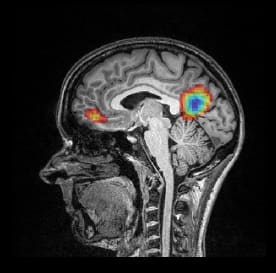

MRI scan of Caroline William's brain. Credit:University of Kansas

MRI scan of Caroline William's brain, showing the areas of the brain involved in sustaining attention. Credit:Boston Attention and Learning Lab